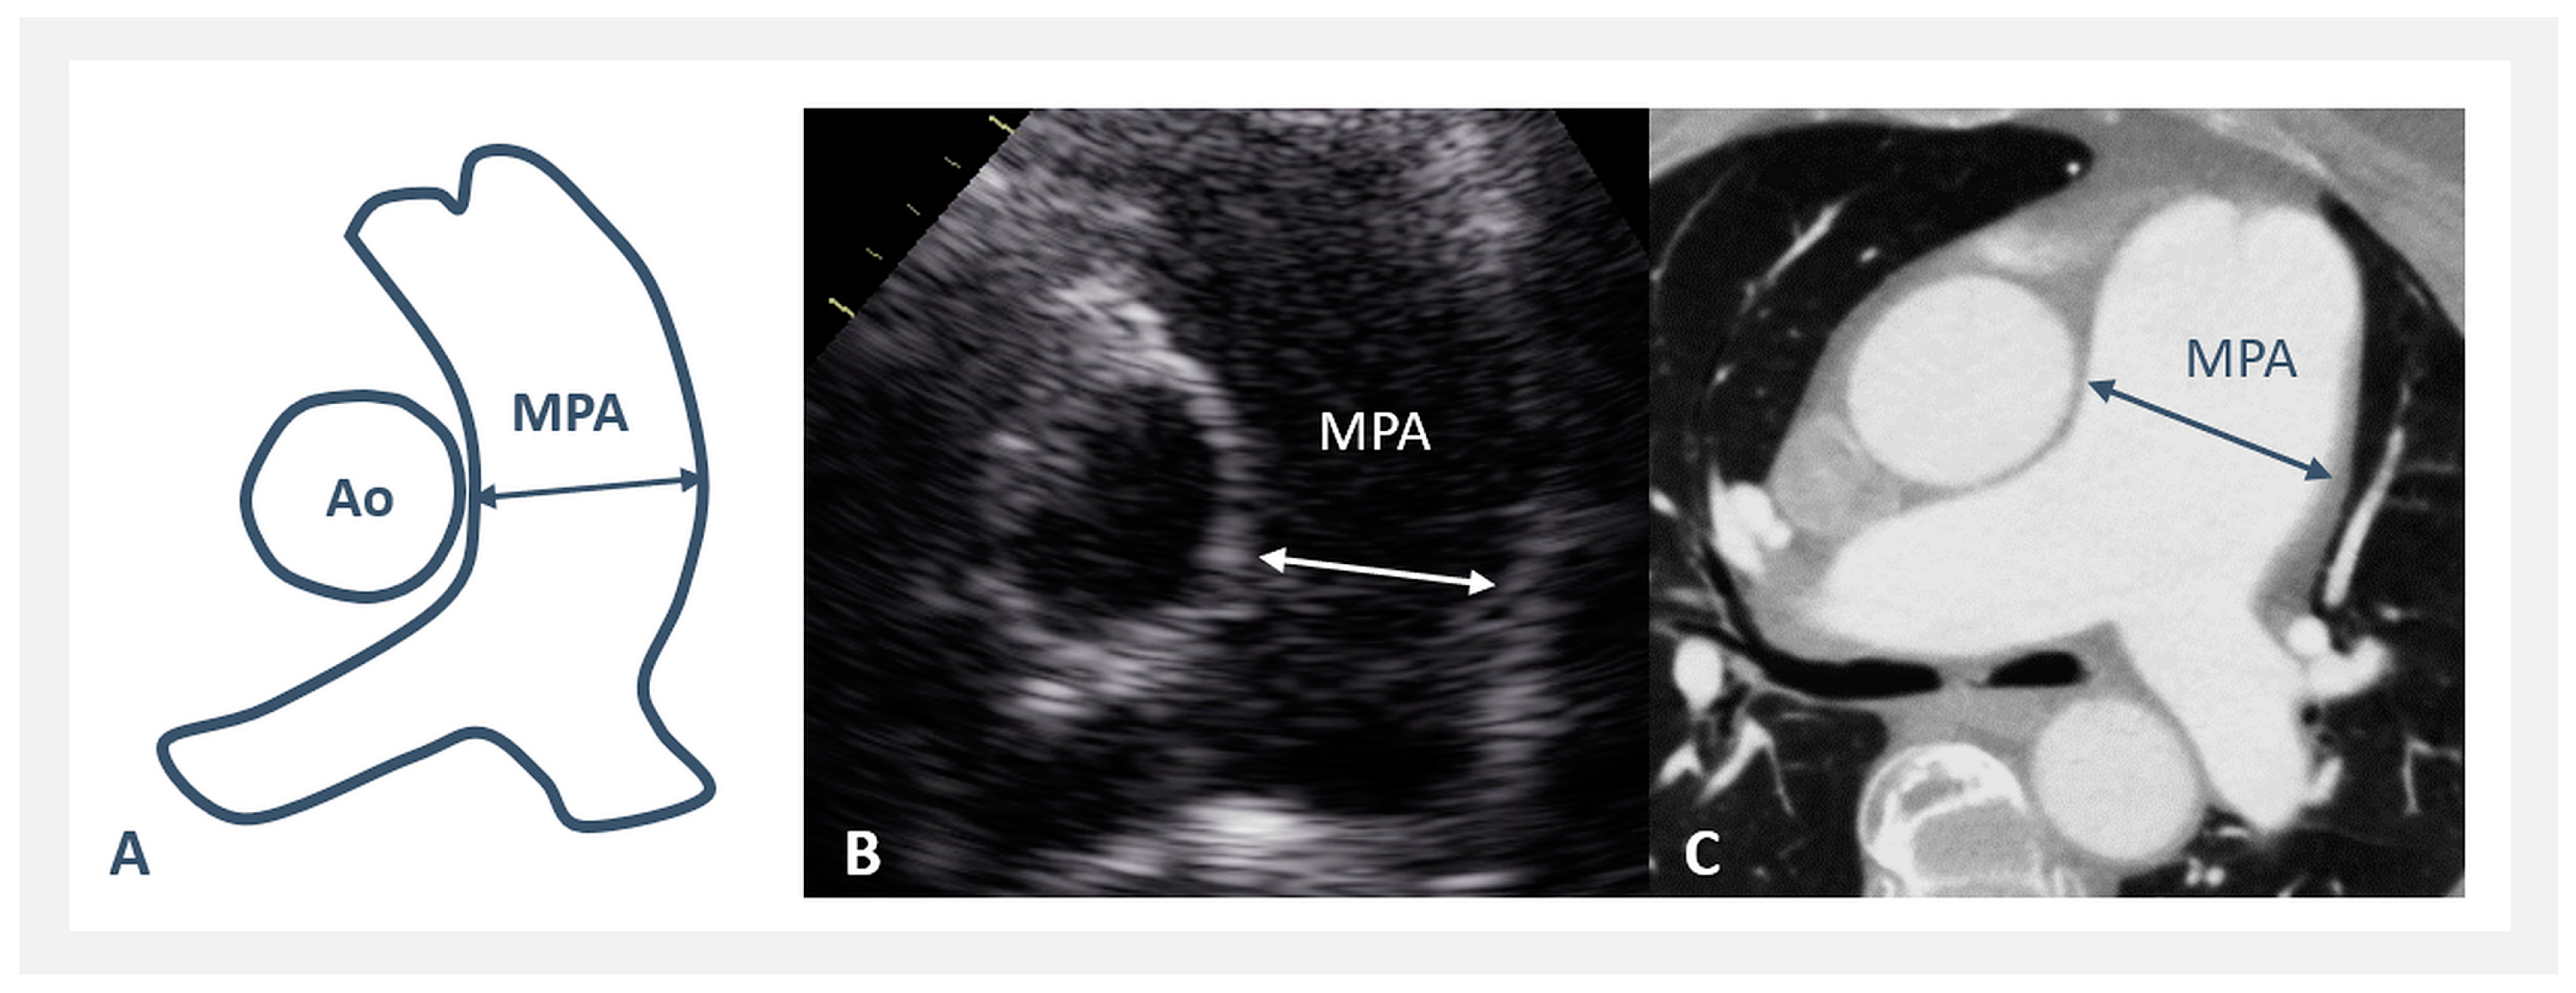

- The MPA/Ao asc diameter ratio was significantly greater in PAH-CHD (0.68–2.3, median 1.3), but not in rTOF/PR (0.46–1.52, median 0.74), compared to NORMAL (0.52–1.09, median 0.8)—Figure 2C. MPA/Ao asc ratio did not show statistically significant changes with age in all 3 patients’ groups, as shown in Figure 3C.